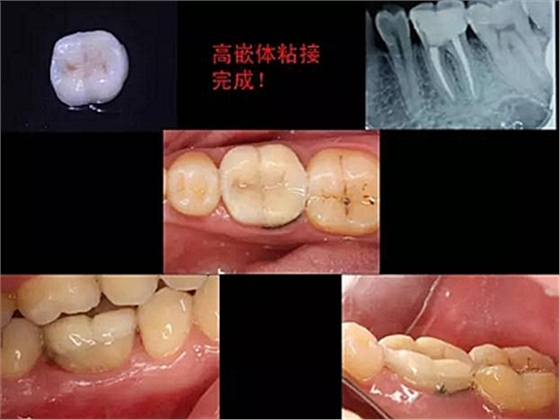

改良垂直褥式縫合關(guān)閉傷口,傷口無明顯滲血,高嵌體預(yù)備完畢后,硅橡膠取模,見邊緣清晰。灌注模型,模型上3MZ350XT分層堆塑高嵌體。

一周后拆除縫線,試戴高嵌體,試戴合適后雙固化粘結(jié)。調(diào)合,拋光。

冠延長手術(shù)和高嵌體修復(fù),本來需要很多次復(fù)診的患者,兩次就診,就把患者難以處理的問題輕松解決了。減少了患者的就診次數(shù)和時(shí)間。